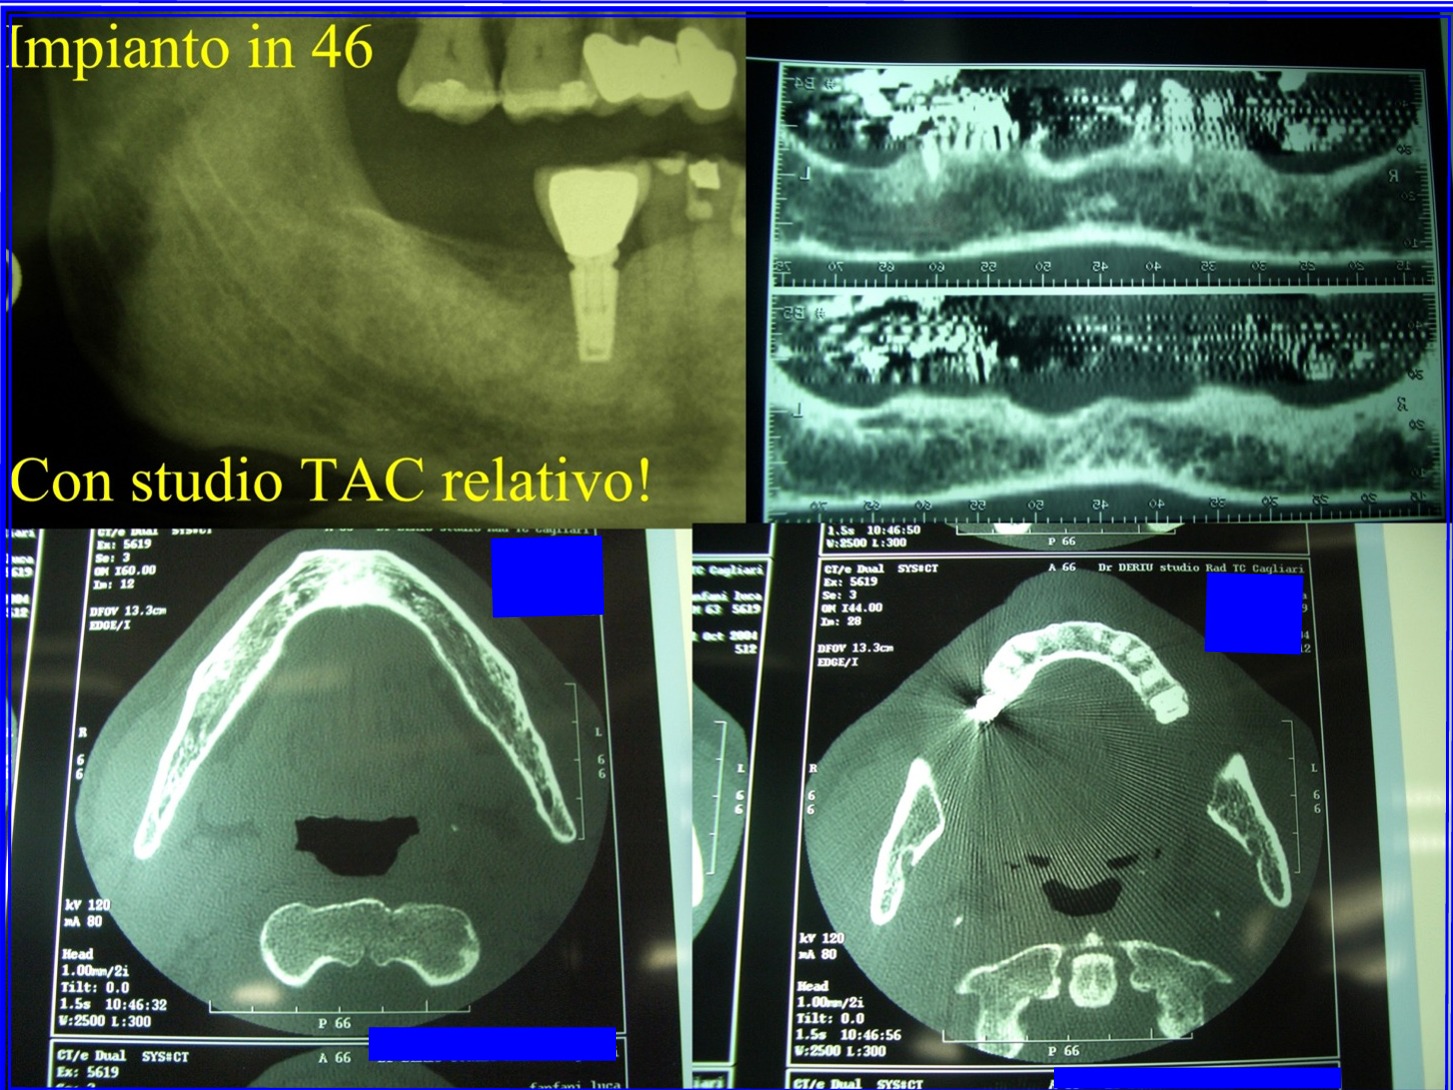

Cara Signora Daniela, questo è il risultato del "concetto" "Impianti a tutti i costi e sempre"! L'implantologia è specialità seria e non è assolutamente la "panacea" di tutti i problemi! Non tutte le bocche o le zone della bocca possono ricevere impianti! Ed in ogni caso per fare implantologia bisogna sempre mettere la bocca in condizioni di riceverli. Invece noto che spesso viene fatta implantologia fine a se stessa senza che parodontalmente ci siano i presupposti di qualità e salute ossea e gengivale idonee e qualità e salute gnatologica e i carichi giusti e tanto altro! Sorge il dubbio che spesso l'impianto venga fatto solo per accontentare la richiesta del paziente che chissà perchè è talmente attratto da esso che è disposto a spendere cifre che non spenderebbe per salvare il suo dente o è disposto come lei a raccontare che un impianto è andato male e pazienza! Se fosse andato male un qualsiasi altro lavoro odointoiatrico sarebbe scattata subito la molla della "denuncia"! Questo non lo capirò mai! Cara Signora, deve capire che l'implantologia è l'ultima "ratio" ed è spesso il risultato del fallimento della terapia odontoiatrica! Quindi in questi casi non è la terapia! ma una "toppa"! Poi ovviamente c'è l'implantologia seria, fatta da implantologi seri che fanno un accurato studio preimplantologico per arrivare a risolvere casi clinici con l'implantologia, altrimenti irrisilvibili, degnamente! Ma questa è tutta un'altra cosa. Cordialmente Gustavo Petti, Parodontologia, Implantologia, Gnatologia e Riabilitazione Orale Completa in Casi Clinici Complessi ed Ortodonzia e Pedodonzia la figlia Claudia Petti, in Cagliari.